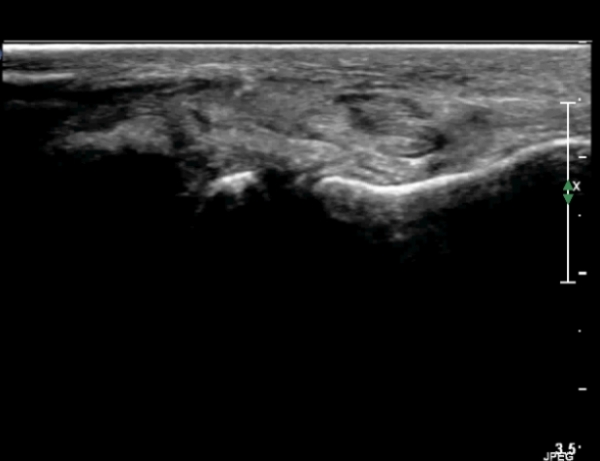

Àü°ÅºñÀδë Á¾´Ü¸é°Ë»ç¿¡¼­ Àü°ÅºñÀδëÀÇ ÆÄ¿­ÀÌ °üÂûµÈ´Ù(»çÁø 4, 5).

Àü°ÅºñÀδë Àü¹æ°ßÀΰ˻翡¼­ ÀÎ´ë ÆÄ¿­¿¡ ÀÇÇÑ °Å°ñÀÇ °úµµÇÑ ¿òÁ÷ÀÓÀÌ °üÂûµÈ´Ù(µ¿¿µ»ó Âü°í)